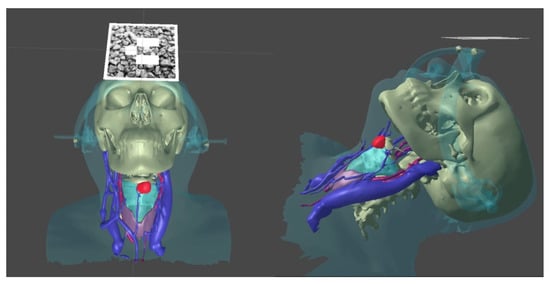

- We transformed the CT into a 3D model using a segmentation approach with respect to the set density threshold or the area of interest in the 3D Slicer. This allowed us to isolate all key anatomical structures of the neck as a series of separate three-dimensional models. After that, resulting 3D models were optimized and cleaned up using the procedural toolkit in Houdini (up to 75–95% polygon reduction); we then transformed the MSCT into a 3D model using a segmentation approach with respect to the set density threshold or the area of interest. This allowed us to isolate all key anatomical structures of the neck separately as a series of three-dimensional models;

- We visualized 3D models using mixed reality smartglasses and the developed software, which has preset parameters for referencing the markers to the three-dimensional model. It has an integrated basic interface [20], which allows the user to display the required anatomical elements as well as customize the parameters of the marker tracking system;